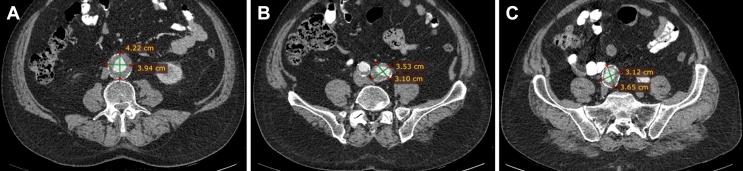

A 65 year old patient underwent EVAR for an aortic and bilateral iliac aneurysms. During the procedure, the right internal iliac artery was intentionally occluded to facilitate treatment of the common iliac aneurysm; however, the left internal iliac artery was preserved. The procedure was uneventful. On the second post-operative day the patient gradually developed symptoms of acute left testicular ischaemia. Clinical and ultrasonographic findings constituted the bases of diagnosis and the patient received conservative treatment with gradual improvement. To the authors' knowledge, this is the ninth case of testicular ischaemia after endovascular aneurysm repair reported in the literature.

一名65岁患者因腹主动脉及双侧髂动脉瘤接受了EVAR手术。术中,为便于治疗髂总动脉瘤,右侧髂内动脉被有意闭塞;然而,左侧髂内动脉得以保留。手术过程顺利。术后第二天,患者逐渐出现急性左侧睾丸缺血症状。临床及超声检查结果构成诊断依据,患者接受保守治疗后症状逐渐改善。据作者所知,这是文献报道的第9例血管内动脉瘤修复术后睾丸缺血病例。